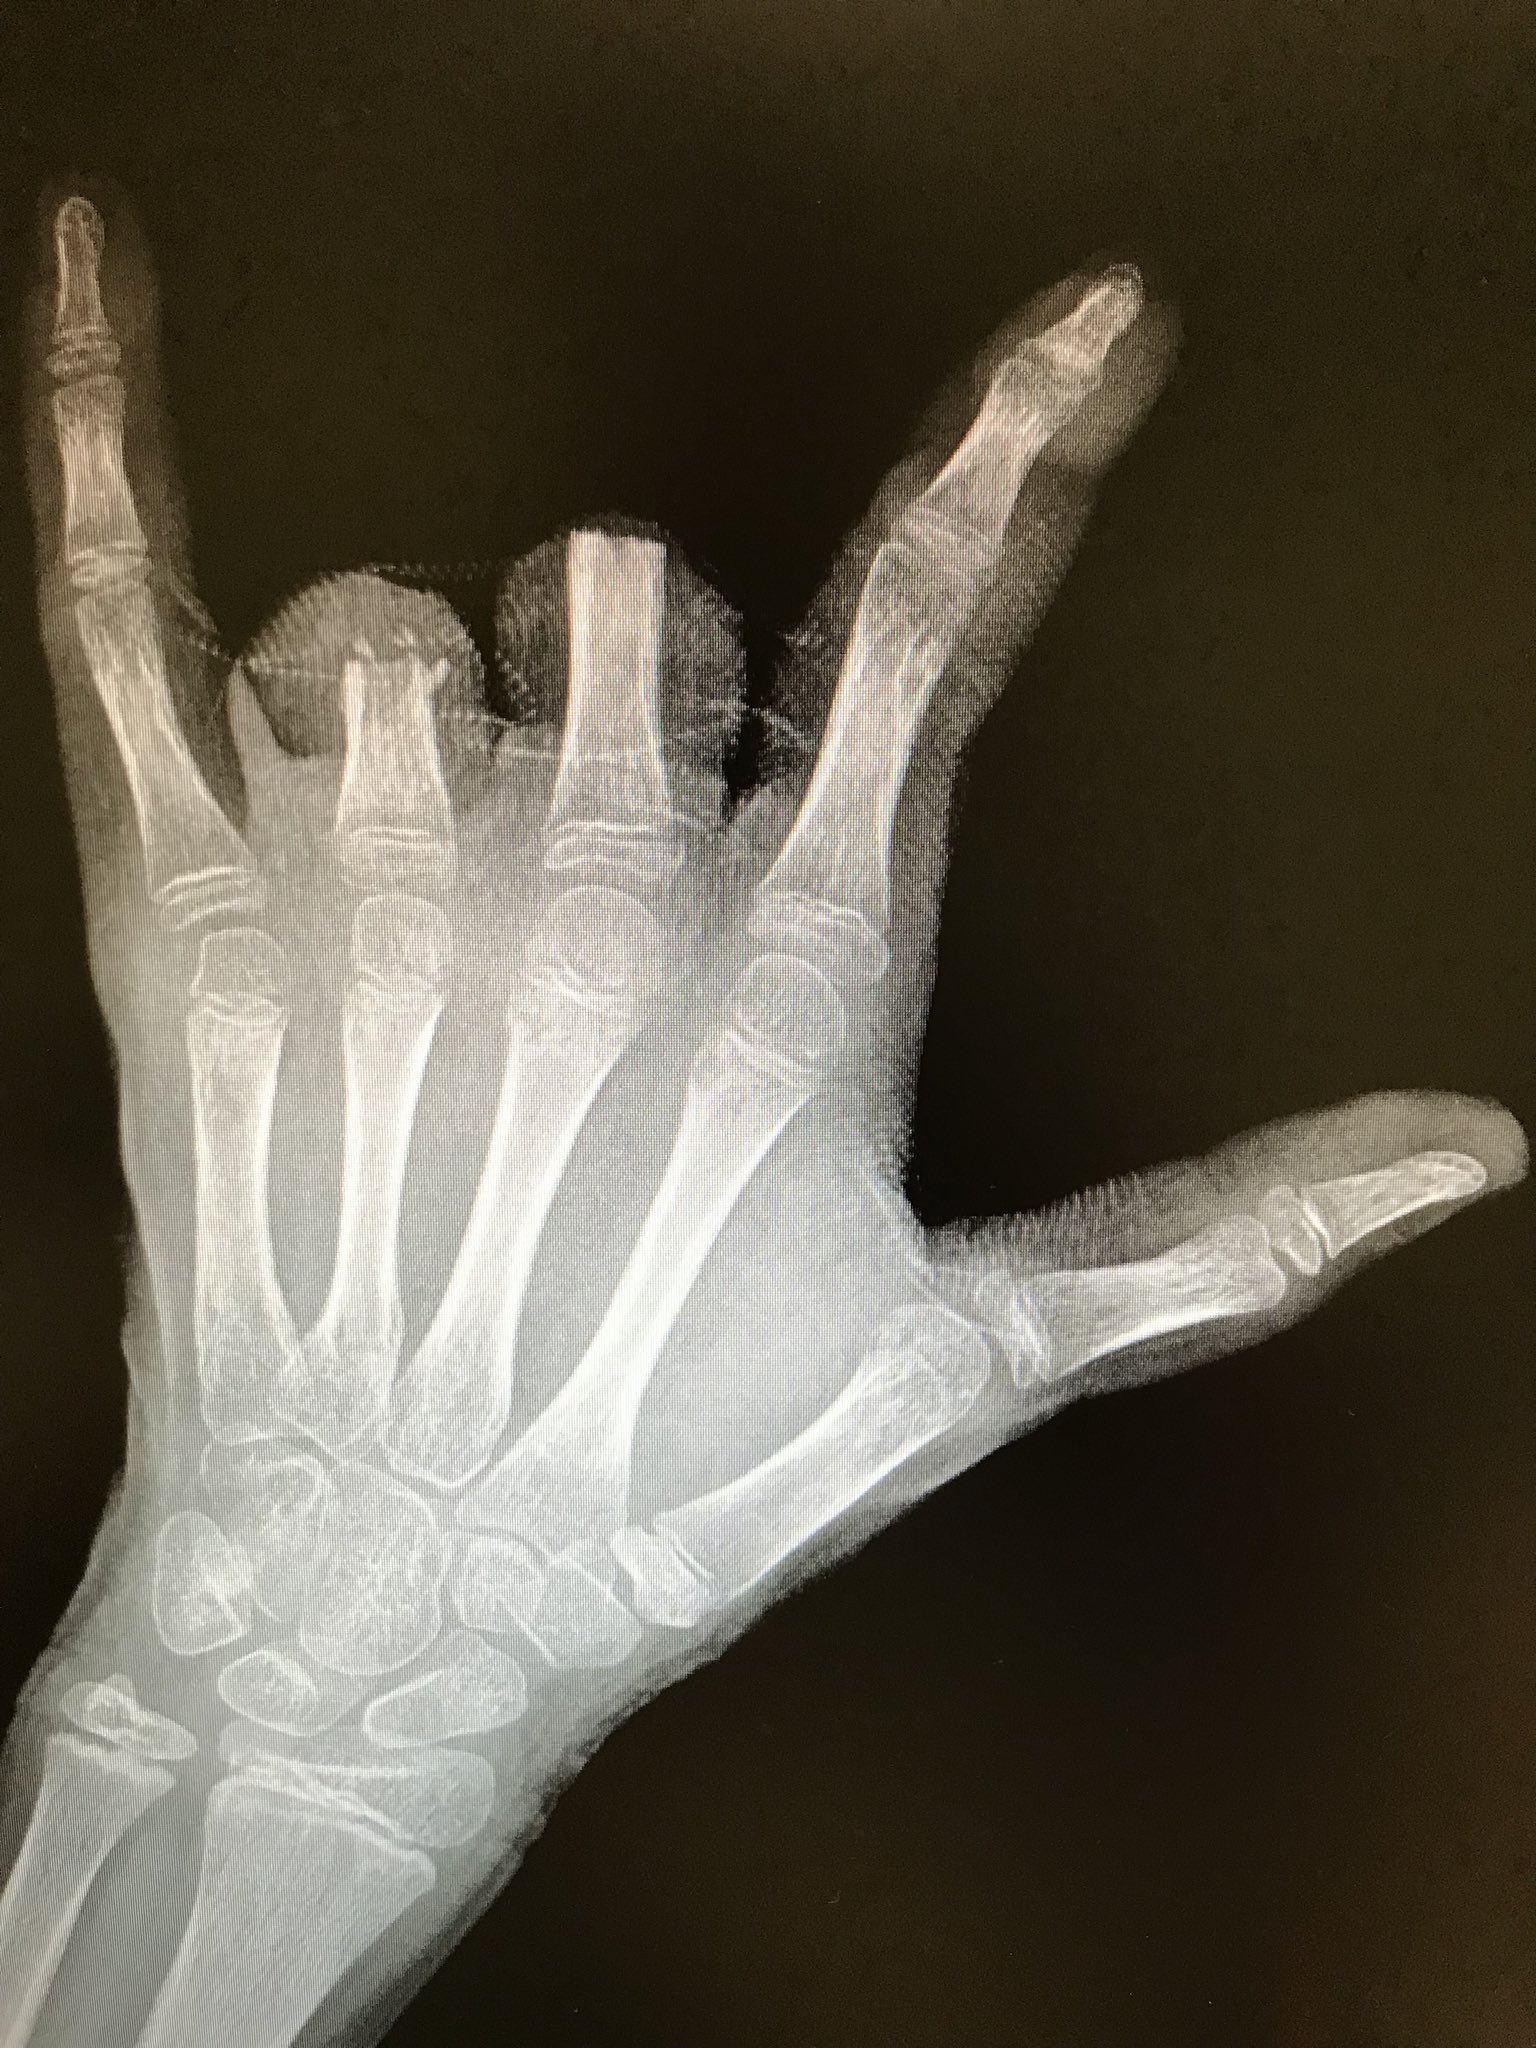

Rescato este caso para sensibilizar acerca del uso de petardos 🧨, sobre todo en niños. En mi opinión, deberían estar prohibidos.